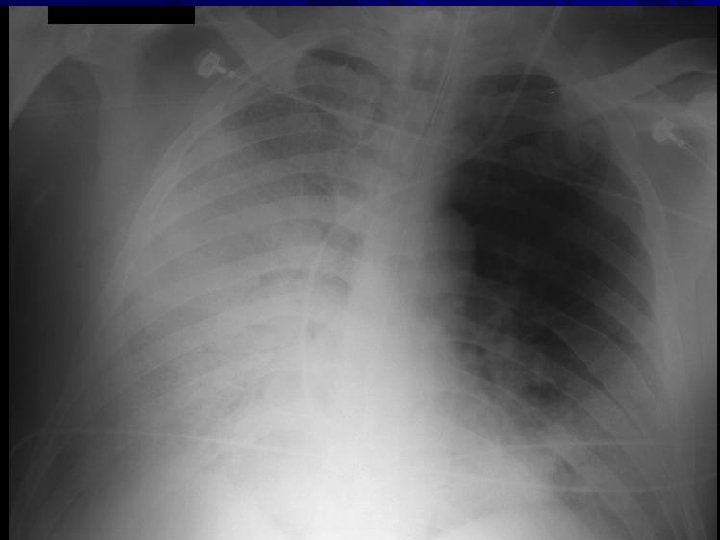

Pneumothorax v v Traumatic Spontaneous -Tall Thin

Pneumothorax Treatment: Immediate Needle Insertion (Second Intercostal Space)

Pneumothorax Treatment: Chest Tube Insertion